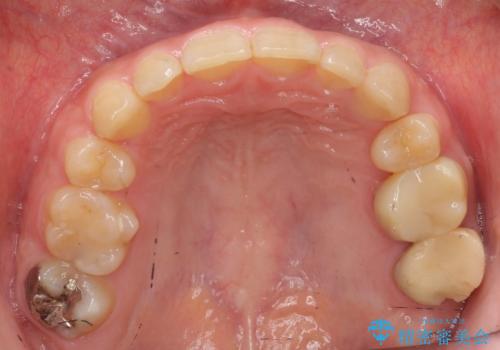

- 上の小臼歯を2本抜歯して矯正を行いました。

今回は上の前歯が内側に傾いている症状があり(Angle Ⅱ級2類)、その修正に時間がかかっています。

ご自身でしっかり装着しなければならないですが、非抜歯で上顎を遠心移動するのであれば、マウスピース矯正も有用な症例だと思います。ただし、右側の2級関係が厳しいため、遠心移動量がかなり大きくなりそうです。どう治すにしても時間がかかりそうな症状です。